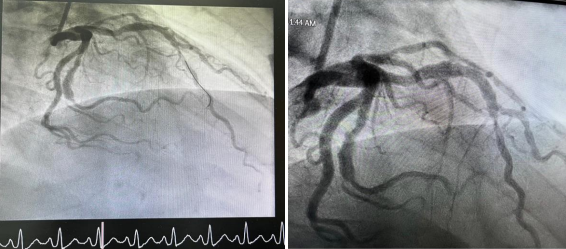

Coronary angiography showed a large caliber ectatic left anterior descending (LAD) artery, which was occluded by thrombus (Figure 1). Despite difficulties in wiring the LAD, the involved segment was successfully ballooned in an escalated fashion, restoring TIMI-3 flow. An ectatic segment that is just distal to the involved segment was also noted, which was studded with thrombus, resulting in a very hazy picture (Figure 2). Although attempts were made to aspirate the thrombus using an Export catheter (Medtronic, MN, USA), it was unsuccessful. Since the patient was symptomatically and hemodynamically stable, a decision was then made to medically manage him for the next 24-48 hours before attempting the procedure again.

The patient was started on intravenous Tirofiban and, after approximately 36 hours, was brought back to the cardiac catheterization laboratory. An improvement in the haziness of the mid-segment left anterior descending artery (LAD) picture was noted, with TIMI-3 flow remaining (Figure 3). Intravascular ultrasound (IVUS) confirmed the presence of an ectatic segment with a large amount of mobile thrombus (Figure 4).

Figure 1: Diagnostic angiogram showing a complete occlusion of LAD.

Figure 2. Baseline Coronary Angiography showing large thrombotic lesion in the LAD (arrows)

Figure 3: Angiogram after intravenous infusion of Tirofiban with partial resolution of thrombus